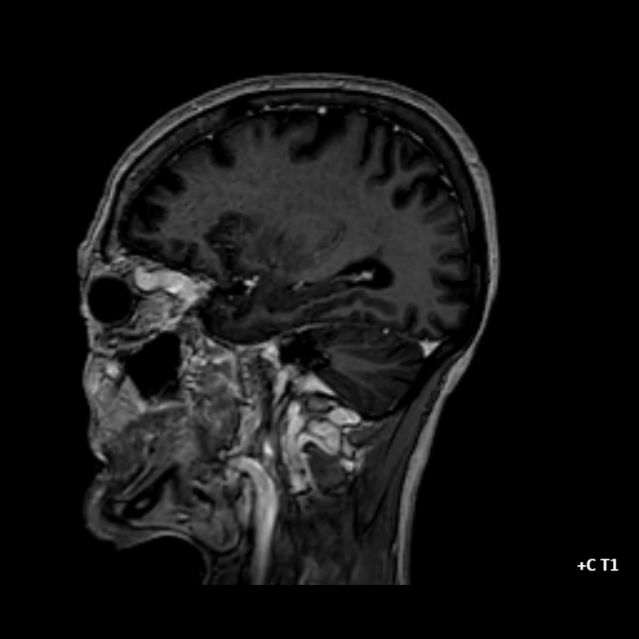

- A) Orbital MRG’de yağ baskılı T2A görüntülerde sol orbital globta ekzoftalmus (ok) izlenmiş olup retrobulbar yağlı dokuda kirlenmeler (ok) ve dilate superior oftalmik ven (ok) dikkati çekiyor. Beyin MRG’de kontrastlı T1A görüntüde sol kavernöz sinüste simetriğine oranla genişleme (ok) izleniyor.

- BT ve MRG: Propitozis, ekstraokuler kaslarda genişleme, superior oftalmik vende genişleme ve tortiyozite, ipsilateral kavernöz sinüste genişleme gösterilebilir. Serebral venöz konjesyonu olan ve intrakraniyal basınçları yükselen hastalarda serebral ödem, hemoraji, leptomeningeal ve kortikal venlerin dilastasyonunu görülebilir. Bunlara ek olarak travmaya sekonder olgularda BT ile eşlik eden fraktürler gösterilebilir.